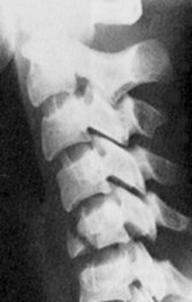

Fractura spanzuratului Fractura anterioara C4 Fractura C5 in lacrima in flexie

"in lacrima"

Fractura C5 "in lacrima" in extensie Luxatie fatetara

C5 - C6 C5 - C6